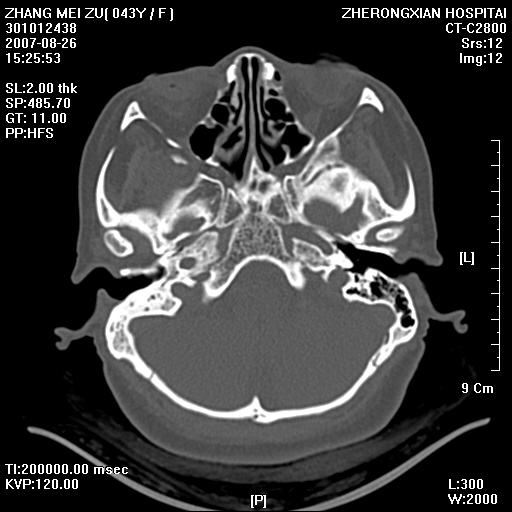

标题: CT9512:F43Y,是肉芽肿还是胆脂瘤?诊断报告该如何出? [打印本页]

标题: CT9512:F43Y,是肉芽肿还是胆脂瘤?诊断报告该如何出?

右耳硬化性乳突炎并鼓窦入口胆脂瘤形成,左侧乳突炎

1, 右侧中耳乳突炎,伴鼓窦入口胆脂瘤形成.

典型胆脂瘤,从上鼓室,乳突窦入口到乳突窦有明显光滑的骨质破坏和软组织结节均为胆脂瘤特点.而肉芽肿对骨质的破坏是轻微的.值得关注的是乳突后壁被破坏只剩薄薄的一层,如果再不尽快治疗,胆脂瘤如果突破其后壁即可能形成耳源性脑脓肿了.